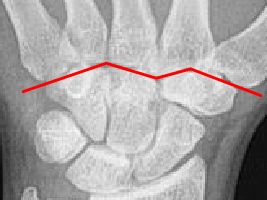

• Kontinuität der drei Karpalbögen:

Proximaler Bogen: proximale Gelenkflächenkonturen von Scaphoid, Lunatum und Triquetum

Mittlerer Bogen: distale Gelenkflächenkonturen von Sacphoid, Lunatum und Triquetum

Distaler Bogen: proximale Gelenkflächenkonturen von Capitatum und Hamatum

Fehlende Abgrenzbarkeit, Versatz oder Unterbrechung sind als pathologisch zu bewerten und deuten auf eine Luxation hin.

• Kontinuität der drei Karpalbögen (vgl. Handgelenk):